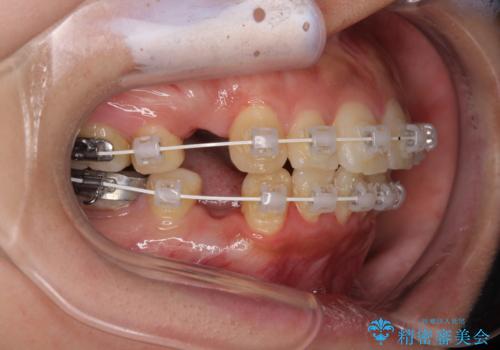

- 審美装置

- 1年7ヶ月

- 10-30回

上下前歯がくちばしのように突出していたため、上下左右の第一小臼歯4本を抜歯し、ワイヤー装置にて矯正治療を行うこととしました。